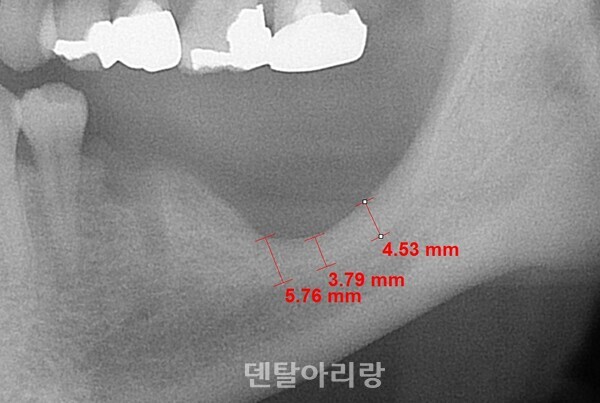

상악골에도 주행하는 다양한 혈관들이 분포하고 있으며, 그 중에서도 상악동의 외측 전면 벽을 따라 주행하는 골내 동맥(intraosseous artery) 가지는 상악동 거상술 측벽 접근법을 위한 골창(lateral window) 형성 시, 출혈을 야기시킬 수 있으므로 주의해야 한다<그림 12>.

△그림 12. 상악동 외측 골내 동맥 가지

시술 중 갑작스럽게 발생하는 동맥의 손상은 예상치 못한 출혈을 야기하며 술자를 당황하게 하고 수술 시야 확보가 어려워져 골이식을 불가능하게 한다. 전기소작기가 구비되어 있다면, 거즈와 석션으로 최대한 출혈을 막으면서 시야를 확보하여 정확히 출혈이 시작되는 점(대부분 출혈 직전, 마지막 골삭제 부위에서 출혈이 시작된다)을 눈으로 확인하고 전기소작기를 이용하여 지혈을 한다. 때에 따라서는 상악동 점막부위의 손상(전기 소작기에 의한 찢어짐이나 천공)이 생기더라도 지혈을 해야 한다. 되도록 이러한 상황을 마주하지 않는 것이 최선이므로 상악동 측벽 골창 형성시에는 동맥을 피하여 형성하여 출혈을 예방하는 것이 좋다.

해부학적으로 상악동 외측벽 골내 동맥은 치조정(alveolar crest)으로부터 평균 약 16mm±3.5mm 상방에서 주행한다고 알려져 있으므로 골창의 상방 골삭제 선이 이 부위보다 하방에 위치하도록 디자인을 설정해야 한다. 상악동 골이식을 위한치조정 접근법은 상대적으로 측벽 접근 방법에 비해 상대적으로 출혈 등 합병증 발생이 적다고 할 수 있으나, 전혀 예기치 못하게 출혈이 간혹 발생하므로 주의가 필요하다. 치조종 접근법 후, 발생하는 출혈은 대부분 상악동 아래 바닥을 주행하는 상악 후상치조 동맥(posterior superior alveolar artery)의 손상과 관련이 있다<그림 13>.